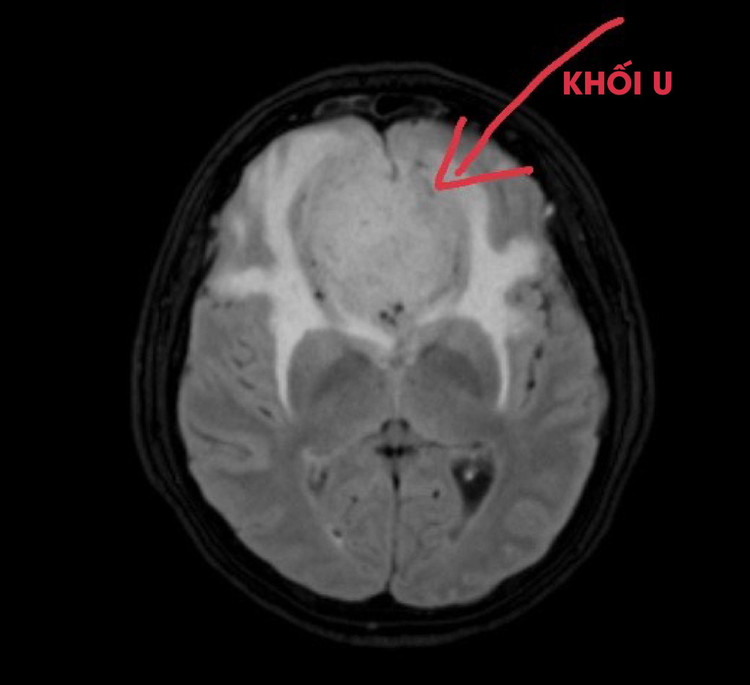

Trong quá trình khám và khai thác tiền sử, biểu hiện bác sĩ đã nghi ngờ bệnh nhân có bất thường về thần kinh nên đã chỉ định bệnh nhân chụp Cộng hưởng từ sọ não. Kết quả chụp của bệnh nhi cho thấy hình ảnh khối u nang vách trong suốt khổng lồ, teo mỏng vỏ não hồi trán trên phải.

| Khối u não ở trẻ trên phim chụp |

Kết quả phát hiện khối u kích thước 52x53mm đề đẩy vùng hạ đồi, giao thoa thị giác, thần kinh thị giác hai bên đoạn sát giao thoa, phù não xung quanh. Hiện tại bệnh nhân đang được điều trị tại bệnh viện và các bác sĩ đã hội chẩn cùng chuyên gia tuyến trung ương để đưa ra phác đồ điều trị phù hợp cho bệnh nhân.